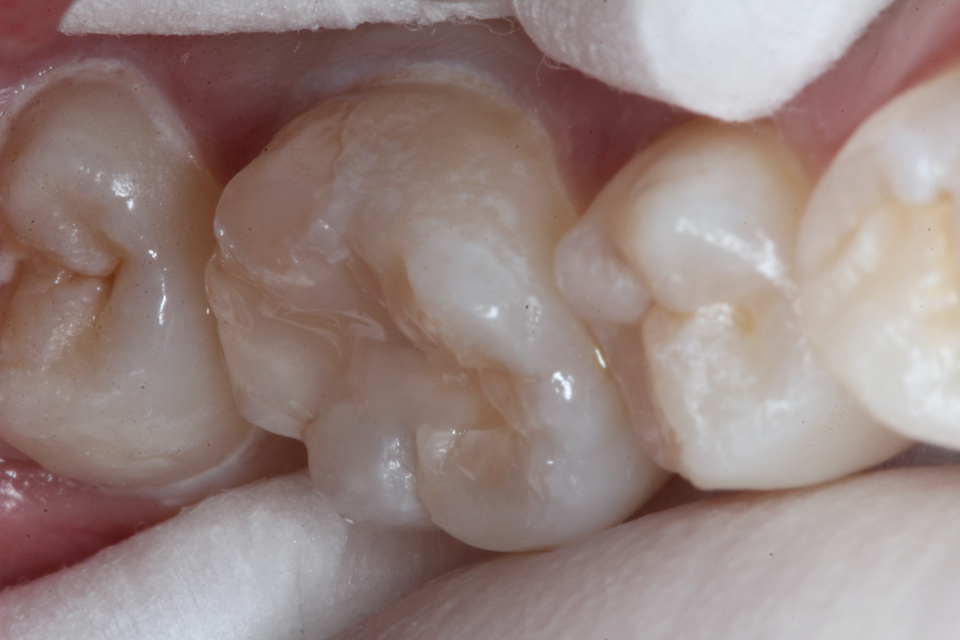

現在14歳女子、右下6、咬合面カリエス、咬合性外傷(食いしばり)、自覚症状なし

元々咬合面に深い溝や窩が歯の発生の過程でできることがあるのだが、そこから象牙質とエナメル質との間のイオン化傾向(自然電位)の差と虫歯の穴の中とその外部の間の酸素濃度差による起電力により虫歯が進行するタイプだ。

さらに外傷性咬合により微細なクラックがエナメル質に入り、虫歯の進行を助長する。